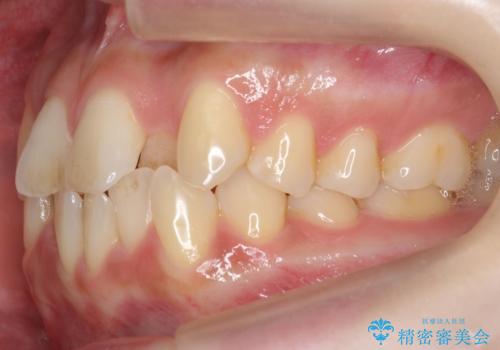

- 前歯のがたつき、受け口を主訴に来院。

上の前歯が二本裏側に入っていました。(反対咬合といいます)

上はワイヤー部分矯正、下はインビザライン(マウスピース)で部分矯正を行いました。

上の前歯のデコボコは激しく、かぶせ物で治療するとなると2本抜歯してブリッジになってしまいます。ダミーの歯の大きさも小さくなるため不自然になり下の歯のがたつきもあるためお勧めできません。